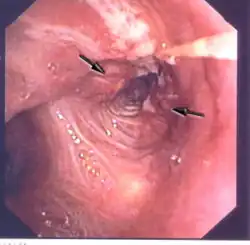

Бронхоскопия (от др.-греч. βρόγχος — дыхательное горло, трахея и σκοπέω — смотрю, рассматриваю, наблюдаю), называемый также трахеобронхоскопией — это метод непосредственного осмотра и оценки состояния слизистых трахеобронхиального дерева: трахеи и бронхов при помощи специального прибора — бронхофиброскопа или жёсткого дыхательного бронхоскопа, разновидности эндоскопов. Современный бронхофиброскоп — это сложный прибор, состоящий из гибкого стержня с управляемым изгибом дальнего конца, рукоятки управления и осветительного кабеля, связывающего эндоскоп с источником света, часто оснащённый фото- или видеокамерой, а также манипуляторами для проведения биопсии и удаления инородных тел.

В современных эндоскопах детальное, четкое изображение с фото- или видеокамеры бронхоскопа передается на экран телевизора (или записывается в компьютер) и затем может быть напечатано при помощи принтера.

- При необходимости проводится фото- или видеосъёмка и запись изображения. При благоприятных условиях через бронхоскоп можно осмотреть не только крупные бронхи, но и разветвления мелких бронхов.